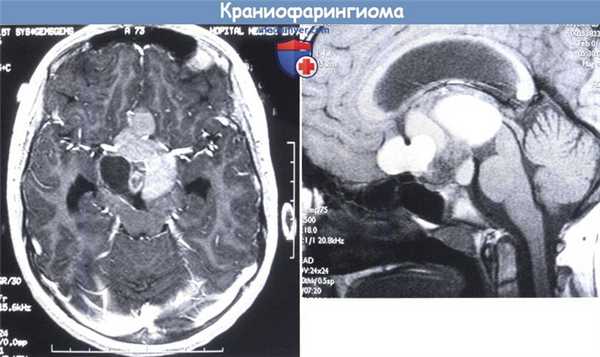

(Слева) МРТ, постконтрастное Т1 -ВИ, сагиттальный срез: в селлярной, супраселлярной, носоглоточной, предмостной области определяется рецидив крупной адамантиноматозной краниофарингиомы, имеющей характерную неоднородную кистозно-солидную структуру. Обратите внимание на масс-эффект опухоли на зрительный перекрест, гипоталамус и мост.

(Справа) МРТ, Т2-ВИ, корональный срез: у двухлетнего ребенка с гигантским супраселлярным объемным образованием определяются множественные гиперинтенсивные кисты. Интраселлярный компонент опухоли имеет относительно малые размеры.